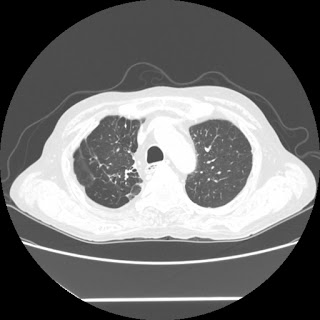

HRCT done on 17Mar16